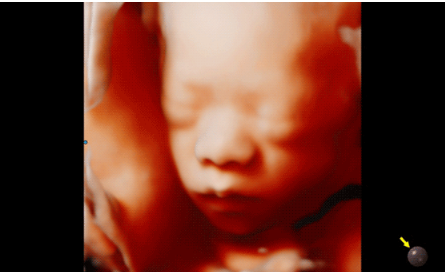

Hera i 10繼承并升級(jí)了全球首款5D超聲“三星麥迪遜WS80A”的“晶體結(jié)構(gòu)”成像理念,即將CrystalBeam?波束形成技術(shù)、CrystalLive?超聲成像引擎、S-Vue Transducer?視覺傳感器集于一身,提供更清晰的圖像。

3D/4D成像方面,Hera i 10通過結(jié)合先進(jìn)的圖像渲染技術(shù),著重加強(qiáng)了邊緣和小結(jié)構(gòu)的可視化能力。